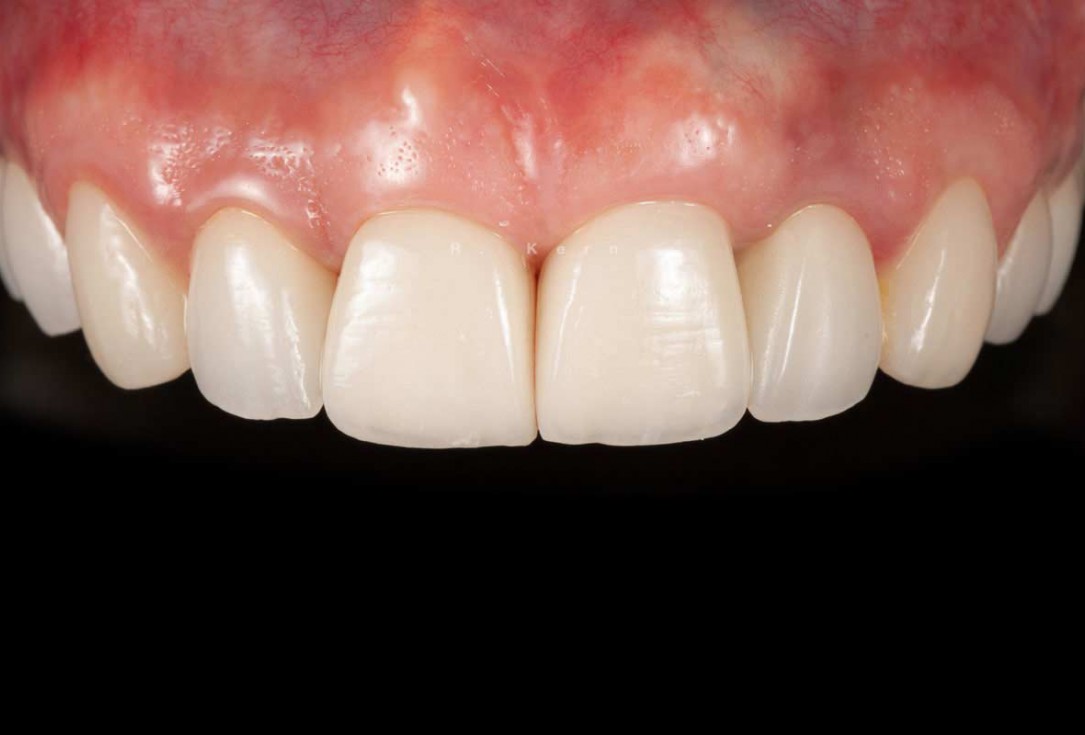

11/12 - Final restoration

Immediate implant placement and periimplant bone augmentation using cerabone® - Dr. R. Kern